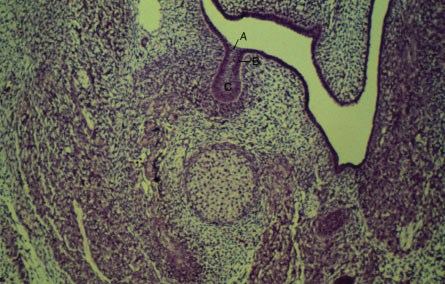

K-slide 3: Still higher magnification

A. Dental lamina

B. Deciduous dental lamina

C. Enamel organ in bud stage

Note also the dental papilla, palatine process and Meckel's cartilag